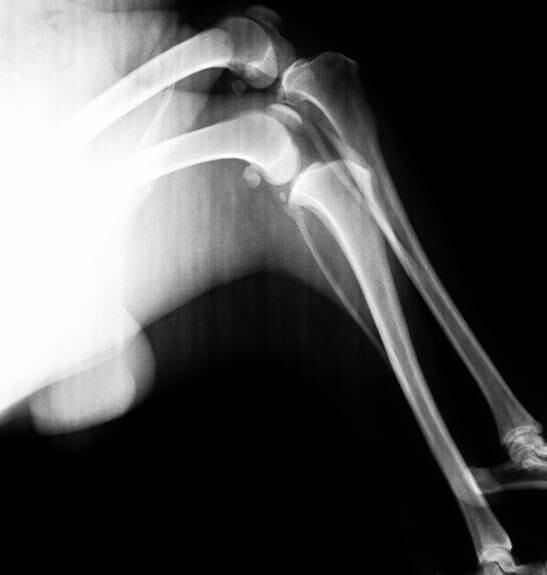

另一患病犬,股骨骨折使用外固定支架演示图。